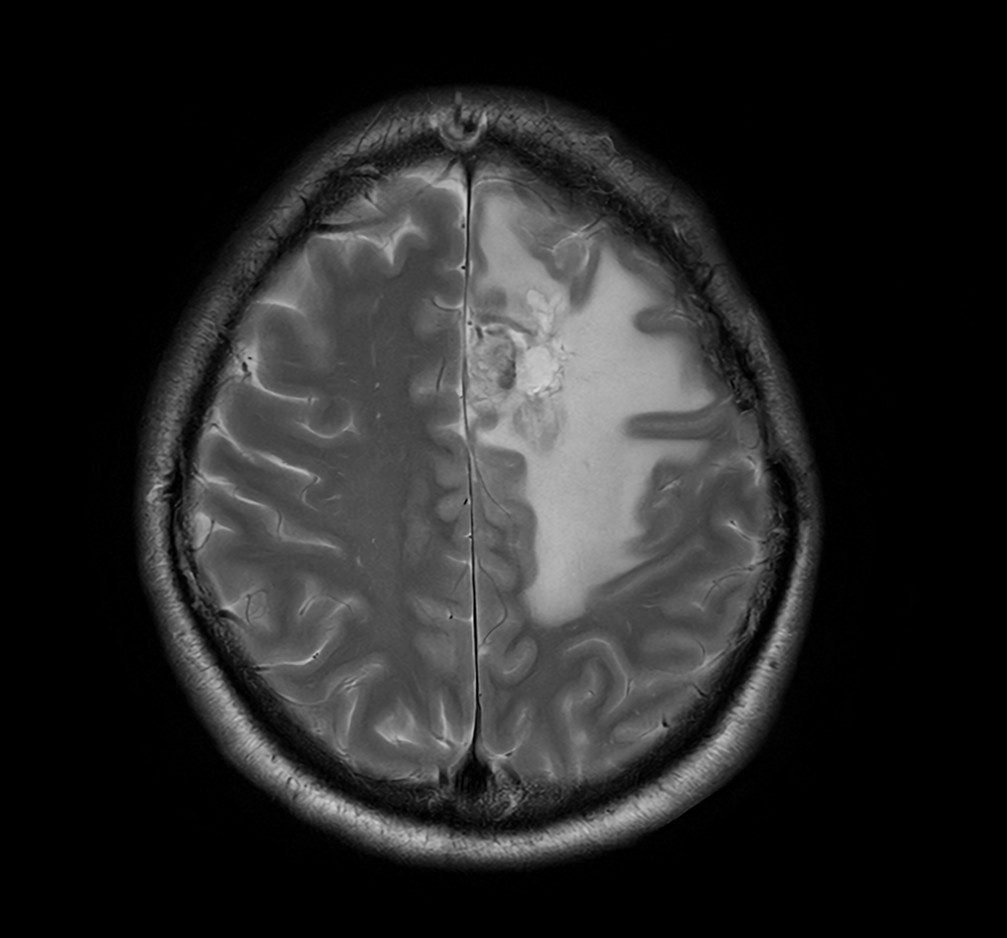

SmartSpeed Precise imaging for brain with glioblastoma

Kyushu University Hospital Japan